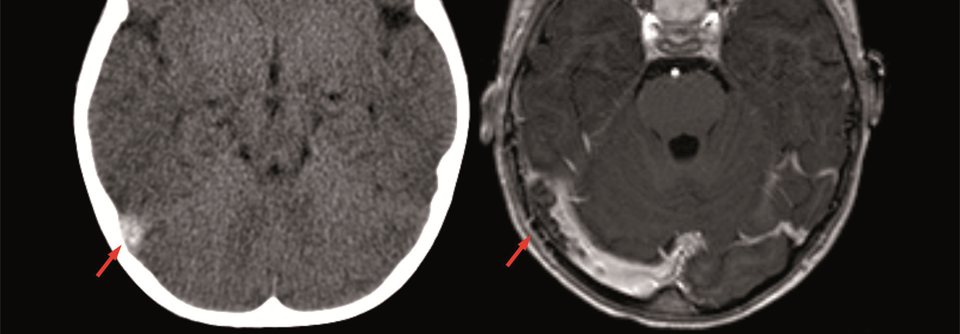

CT ohne und MRT mit Kontrastmittel zeigen beide den Befund einer SVT (Pfeil) beim selben Patienten.

CT ohne und MRT mit Kontrastmittel zeigen beide den Befund einer SVT (Pfeil) beim selben Patienten. © wikimedia/Hellerhoff